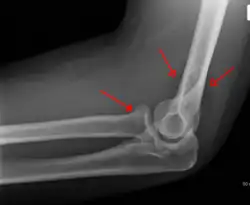

La fracture peut se produire dans la capsule de l'articulation du coude. Elle n'est pas nécessairement visible directement sur une radio mais peut être détectée par le déplacement des coussinets adipeux à la suite de l'épanchement articulaire par le "signe du voile".